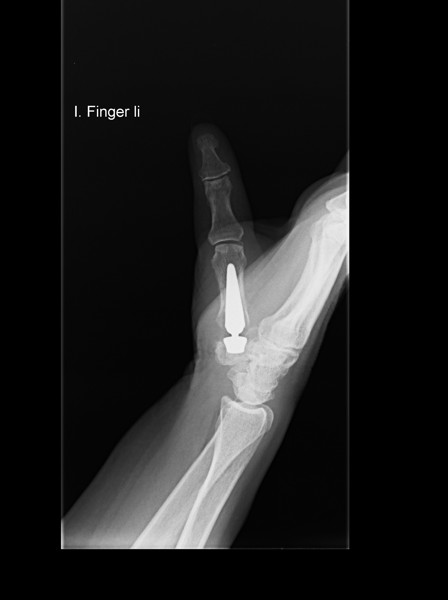

Eines dieser Verfahren ist der Einsatz einer Daumensattelgelenksprothese (Duokopfprothese). Sie hat anderen Eingriffen gegenüber wesentliche Vorteile, da Ihre Hand nach der Operation wieder schneller beweglich sein wird. Zudem verbessert sich Ihre Griffkraft und Sie werden schneller arbeitsfähig sein.

Rhizarthrose Behandlung mit einer Daumensattel-Gelenksprothese